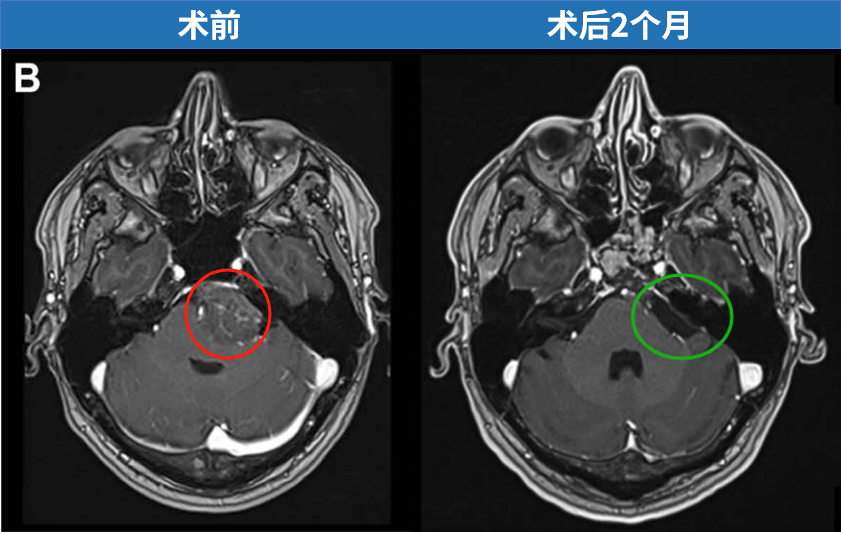

诺亚术前影像,左侧岩斜区脑膜瘤,呈不均匀强化。

福教授选择经鼻内镜手术——兵分两路:先通过血管栓塞术切断肿瘤的"粮草供应",再采用先进的单鼻孔内镜技术精准切除。

最终,在INC福教授的定制化手术策略之下,从术前栓塞、入路考量到实施手术,无需开颅,仅右侧单鼻孔入路,一双“筷子”便成功全切肿瘤。脑干复位良好,未见脑嵴液漏及新发神经功能障碍,术后一天下地,术后一周顺利出院。关闭术腔时,以腹部脂肪填塞硬膜内腔及蝶窦,并缝合鼻黏膜,表面覆盖硅胶片保持湿润;硅胶支架留置4周后取出。